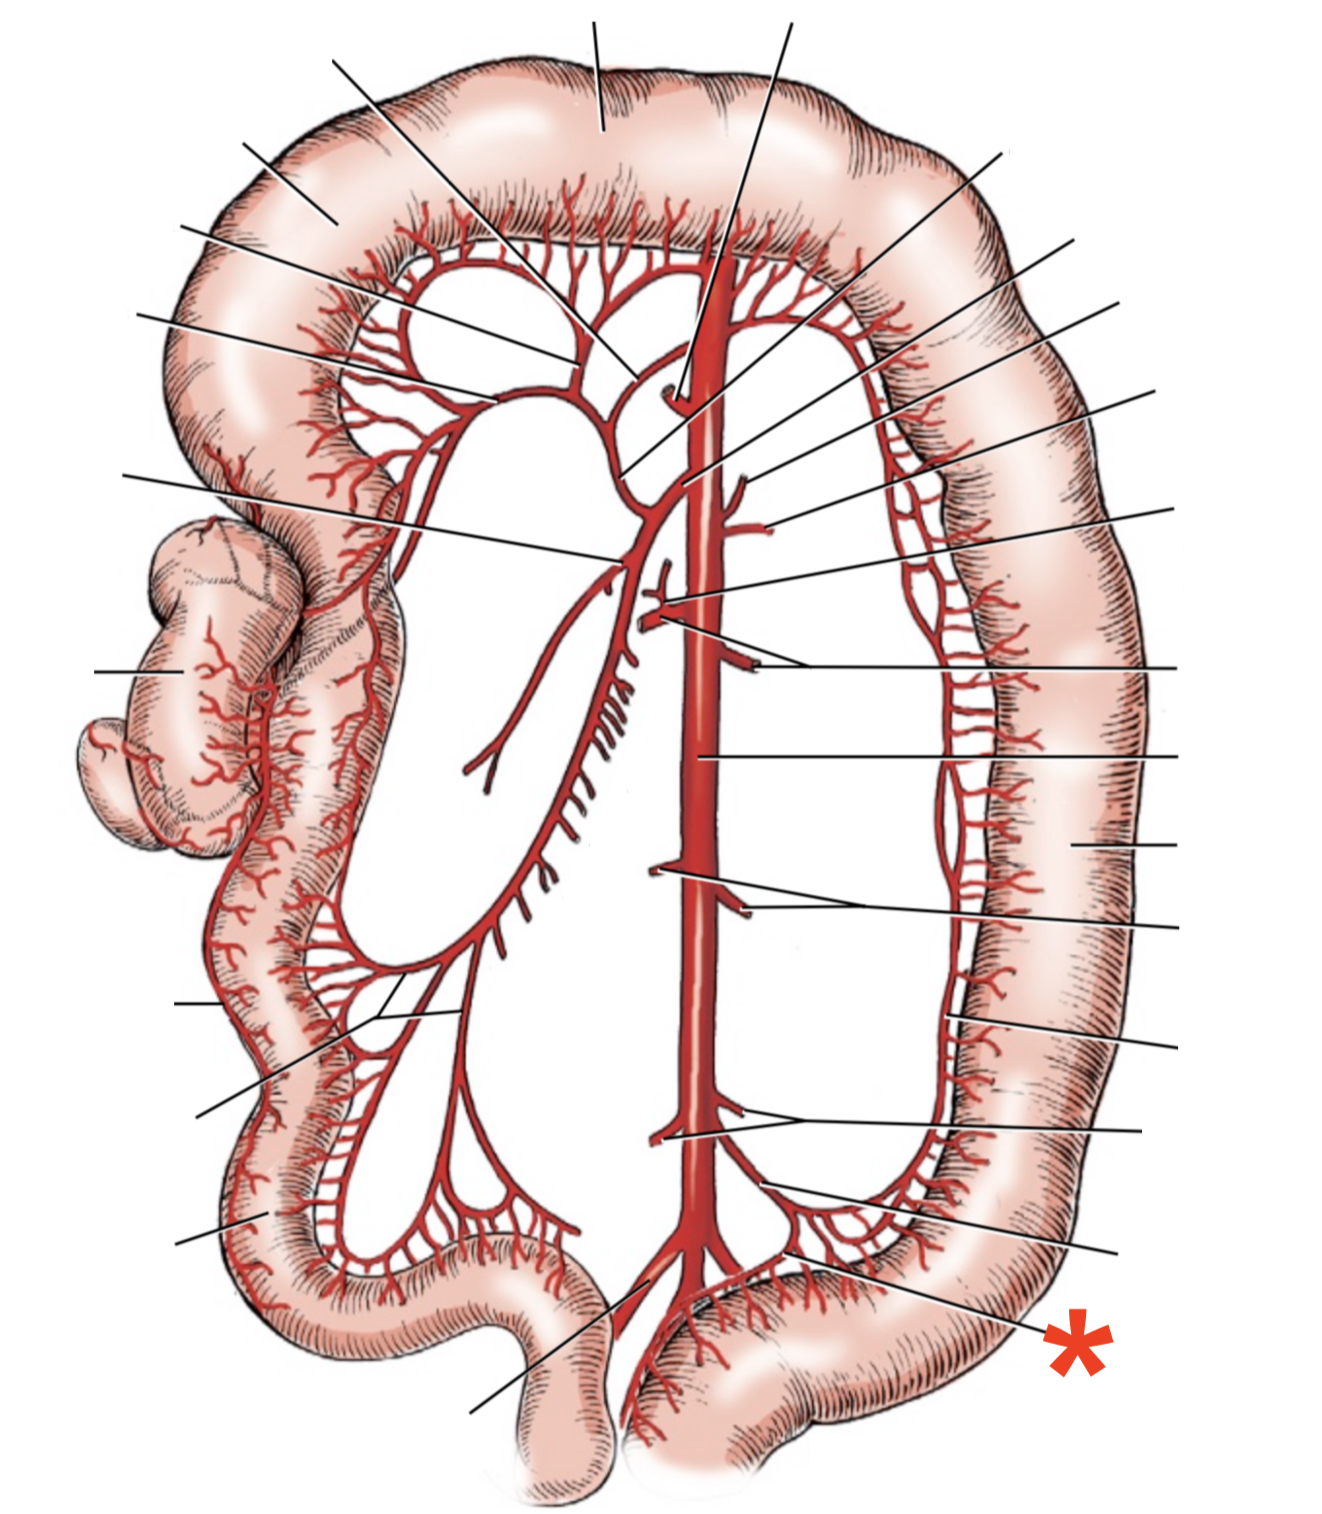

A

A. mesenterica cranialis

A

A. mesenterica caudalis

A. pancreaticoduodenalis caudalis

A

Aa. jejunales

A

A. ilei

- Anastomises with r. ileus mesenterialis a. iliocolica

A

A. ileocolica

A

A. colica dextra

A

A. colica media

A

A. mesenterica caudalis

A

A. colica sinistra

A

A. rectalis cranialis

A

A. ileocolica

**A.** **caecalis**

**R.** **ilei** **mesenterialis**

List the branching of *a.* *mesenterica* *caudalis*

* *A. colica sinistra*

* *A. rectalis cranialis*

List the branches of *a.* *mesenterica* *cranialis*

* *A.* *pancreaticoduodenalis* *caudalis*

* *Aa. jejunalis*

* *A. ilei*

* Common trunk

* A. colica media

* A. colica dextra

* *A. ileocolica*

* *R. ilei mesenterialis*

* *A. cecalis*

* *R. colicus*